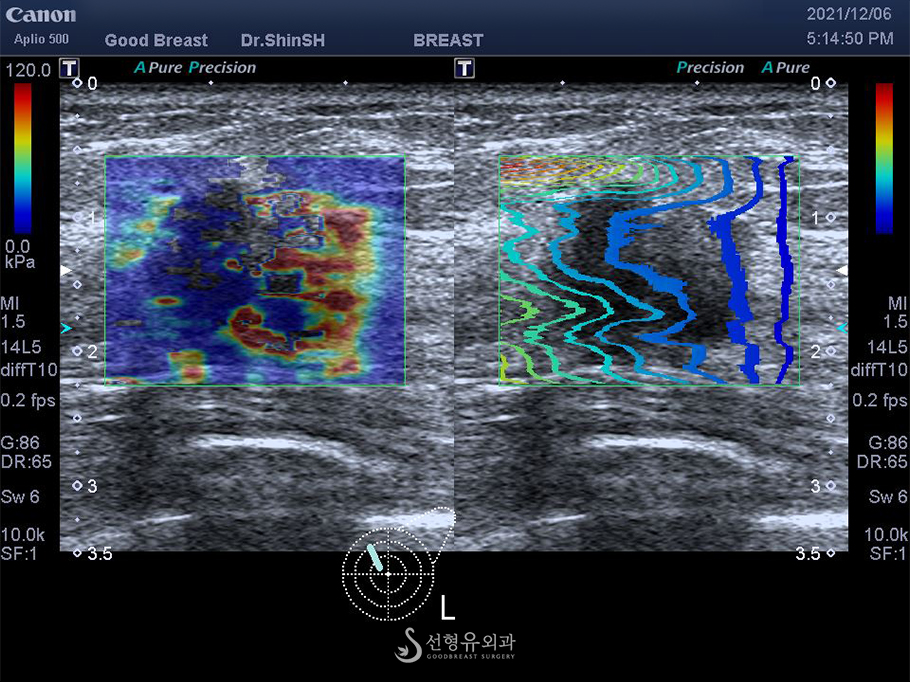

과거에는 초음파 영상으로 혹의 크기와 모양 정도만 확인하였지만 최신 초음파 기계장치는 여러 기능이 탑재되어 단단한 정도와 미세석회병변까지 찾아낼 수 있습니다.